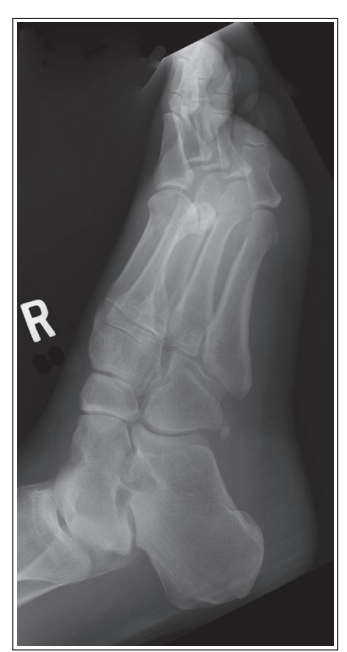

What is the issue with this oblique foot?

First digit of the phalanx is superimposing with 2nd and third

Over-rotation with more than 45 degrees obliquity